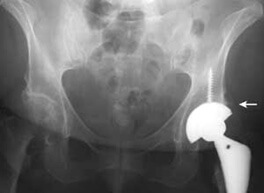

A completely artificial replacement of the damaged joint, known as a joint prosthesis, is classified as a Total Hip Arthroplasty or simply Total Hip. This means that the articular surfaces of the acetabulum and the femur are replaced.

All invasive procedures carry risk. Looking at Total Hip Arthroplasty for example, as the most invasive of the treatments for osteonecrosis, the possibilities include infection, blood clots, bleeding, anesthesia risks, and medical risks not directly due to the invasive procedure. Certain hip-specific risks, like infection at the surgical site, are typically less than 1.5 percent for total hip replacement. The complication of dislocation, where the femoral head comes out of joint, is reported to be less than 1 percent. Overall, the frequency of major complications following total hip replacement surgeries is regarded as low (Leopold, 2003).

Later risks associated with total hip surgery include the possibility that the prosthetic device may loosen from the bone and that late infections or dislocations may occur. However, numerous studies have shown that a technically well-performed total hip replacement is more than 90 percent likely to be in service and functioning well more than 10 years after the surgery, and some sources report full function in as much as 80 percent 20 years after surgery (Leopold, 2003), (Total Hip Replacement, 2003).